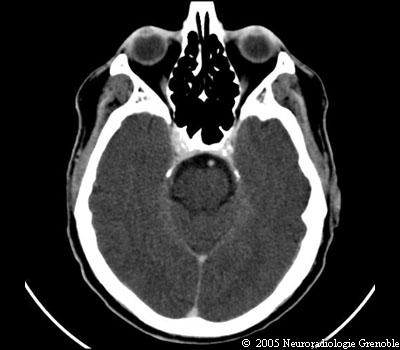

Radioanatomie TDM de l'encéphale

TDM cérébrale sans injection